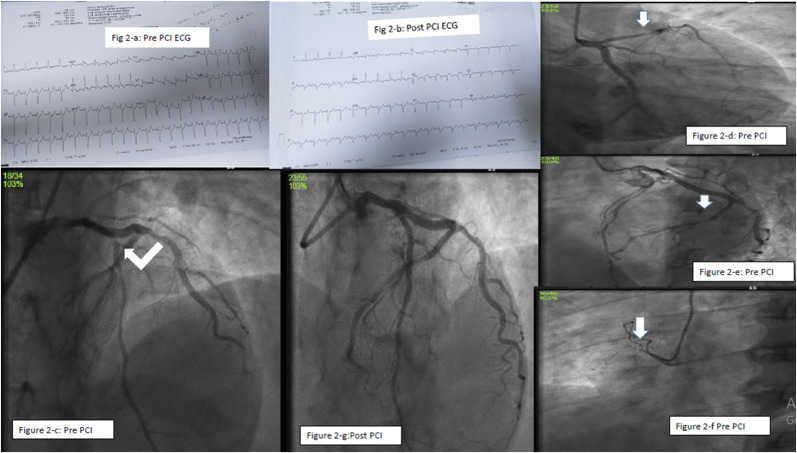

Case-2: A 48-year-old male patient presented with complaints of severe chest pain associating cough and sweat. He had diabetes and hypertension for 4 years. He is on treatment for branch vessel coronary artery disease (CAD) for 3 years. History disclosed that he had received his second dose of COVISHIELD Covid vaccine 6 days before. His Blood pressure (BP) was 170/80 mm Hg with Pulse rate (PR) of 142/min. Lipid profile is suggestive of dyslipidemia (Low density cholesterol (LDL-C) 207mg%, High density cholesterol (HDL-C) 40mg%, Triglycerides (TGL-C) 172mg%) with normal platelet count of 257 10³/mm³ and high sugar level. ECG showed SR, 142/min with ST elevation in V1–V2, avR with qR in lead I and avL (Fig. 2 -a, 2-b). Echo revealed RWMA involving mid anterior wall, mild to moderate LV dysfunction, LVEF-45%, mild mitral regurgitation (MR). He was loaded with antiplatelet, statins in the emergency ward and was taken up for Emergency CAG, which showed Double vessel disease (DVD). The culprit vessel LAD had thrombus containing 95% proximal stenosis and distal LCX had 70% lesion (Fig. 2-c, 2-d, 2-e, 2-f). Adhoc primary PCI to LAD (Fig. 2-g) was done using 2.5 × 48 mm XIENCE XPEDITION stent and was discharged after 2 days.

Figure 2.

a: ECG showing antero-septal myocardial infarction (ASMI) prior to PCI Figure 2-b: ECG showing evolved ASMI after PCI

Figure 2-c-d: LCA angiogram showing severe disease of proximal LAD

Figure 2-e: Left coronary artery angiogram (LCA) showing severe disease of distal LCX

Figure 2-f: RCA showing 100% occlusion of proximal non-dominant RCA

Figure 2-g: LCA angiogram showing well opened up proximal LAD after stenting